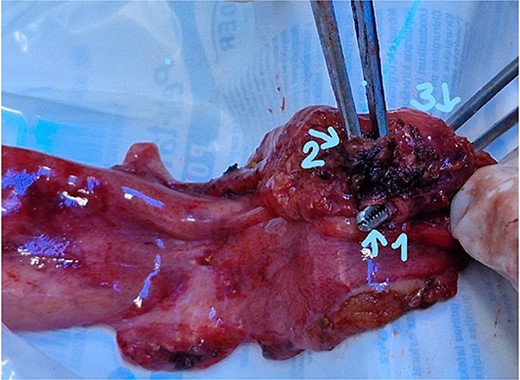

The patient was scheduled for a laparoscopic cholecystectomy the following day. Intraoperatively, an enlarged gallbladder hydrops with the presence of various caliber calculi in the lumen, the largest of which measured 2 cm/d, was found. The contents of the bladder are punctured and evacuated to facilitate its grasping in the fundus area and creating a good exposure of Callot’s triangle. Using a four trocar technique, a dissection was performed in the triangle of Callot, noting the difficult manipulation in the area between cystic duct and common hepatic duct. The cystic duct is identified to its confluence with the common bile duct at a 45° angle. The cystic artery was also visualized, after which clips were placed on both structures after ensuring that they entered the gallbladder. Dissection of the gallbladder in its distal part, attached to the liver parenchyma above Rouvier’s line, was started using electrocautery and hook. The tissue density of a limited area in the distal part between the wall of the gallbladder and the liver parenchyma was dissected using a hook. A bile duct was opened in its unusual anatomical location (Fig. 1). Due to lack of equipment for intraoperative cholangiography, it was converted to open access and subsequent revision of the extrahepatic bile ducts. The common bile duct and right–left hepatic duct were mobilized to the site of entry into the liver parenchyma. A parietal lesion of the right hepatic duct just above the confluence and anatomical integrity of the common bile duct and left hepatic duct were found. After examining the removed gallbladder, it was found that it was immediately flowing into a duct which connects the cystic duct with the right hepatic duct as depicted in Fig. 2. A plasty of the right hepatic duct was performed, and prior to this duodenotomy and papillotomy were performed by mobilization of the duodenum according to Kocher. A protective drain was placed in the choledochus draining from the right hepatic duct to the ampulla of Vater. Separetely, the clips previously placed on the cystic duct were removed and a transcystic drain was placed; a leak test was performed at the plastic site of the right hepatic duct. The postoperative period was without complications. From the transcystic drain, the secretion of bile stopped on the fourth postoperative day. On the eighth postoperative day, transdrainage cholangiography was performed; the common bile duct and bought hepatic ducts were imaged, and free passage of the contrast material through the duodenum was established (Fig. 3). The transcystic draine was removed on the 20th day of surgery.

Gallbladder (1) distal part ot the cystic duct; (2) the part connecting with the right hepatic duct; (3) entrance to cystic duct from the lumen of the gallbladder.